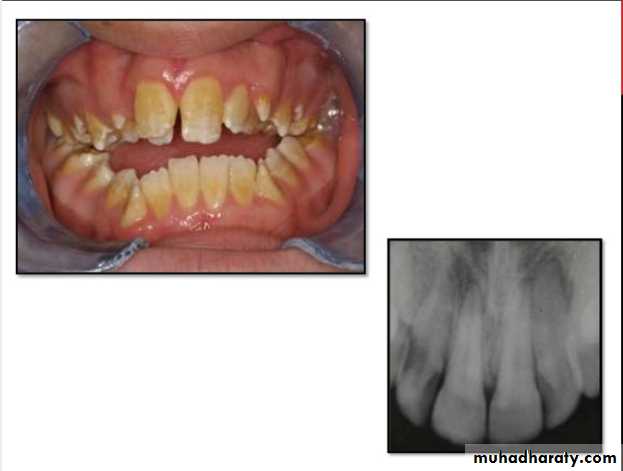

Amelogenesis Imperfecta

*It is a developmental disturbance that interferes with normal enamel formation.*It leads to marked changes in the enamel of all or nearly all the teeth in both dentitions.

*Most forms are autosomal dominant or recessive.

*Affects both dentition.

Enamel is composed mostly of mineral that is formed and regulated by the proteins in it. Amelogenesis Imperfecta is due to the malfunction of the proteins in the enamel.

* Classified based on pattern of inheritance:hypoplasia.

hypomaturation.

hypocalcified.

* No treatment except for improvement of cosmetic

appearance.

Hypoplastic Amelogenesis Imperfecta:

* Due to some defect in ameloblasts enamel fails to develop to its normal thickness dentin exposed the tooth shows yellowish-brown color.*Enamel is randomly:

pitted .

rough OR smooth &glossy.

*The occlusal surfaces of the posterior teeth are relatively

flat with low cusps due to attrition of cusp tips that were initially low and not fully formed. An anterior open bite may be noted. defects become stained but teeth are not especially susceptible to caries unless enamel is scanty and easily damaged.

Generalized hypoplastic type

Amelogenesis ImperfectaAffects primary &permenant dentition

Severe mottling of the enamel surface.

Hypomaturation Amelogenesis Imperfecta:

*Enamel is normal in form on eruption but:

opaque.white to brownish-yellow.

softer than normal.

tends to chip from underlying dentin.

Radiographically:

Affected enamel exhibits radiodensity similar to dentin.

Hypocalcified Amelogenesis Imperfecta:

*Enamel matrix is formed in normal quantity,poorly calcified.

When newly erupted:Enamel is normal in thickness, normal form, but weak , and opaque or chalky in appearance.

With years of function:

Coronal enamel is removed except for cervical portion that is occasionally calcified better.

Density of enamel & dentin are similar.